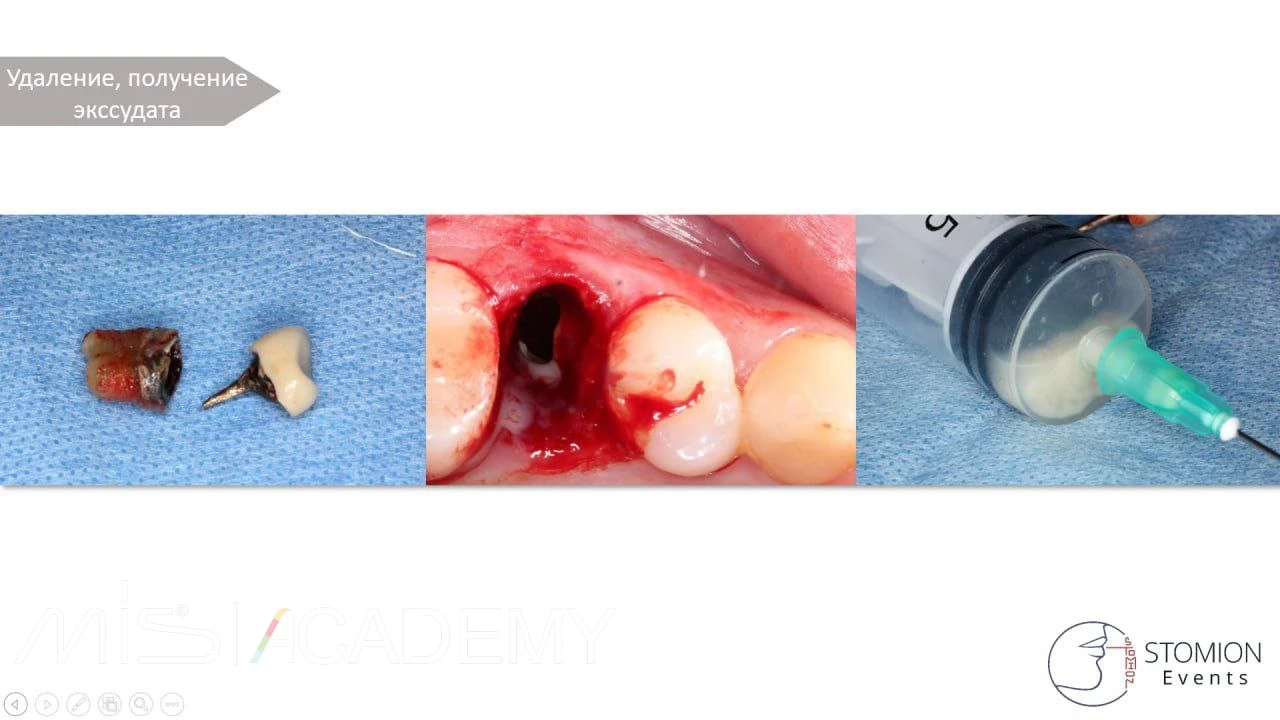

— Под местной анестезией провели удаление 2.5, пункцию кисты, получили обильный гнойный экссудат.

— Выполнили активное промывание физ. раствором до чистых вод.